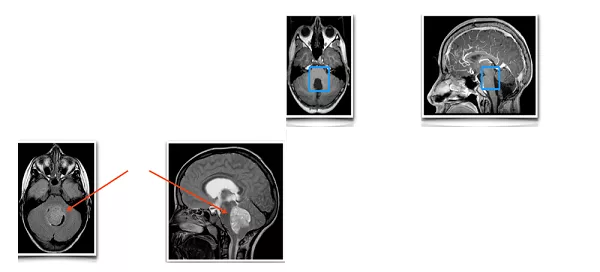

儿童髓母细胞瘤位置在哪儿?有文献报道髓母细胞瘤多发生于小脑半球,但也有作者报道发病率由高到低依次为四脑室、小脑半球及小脑蚓部。